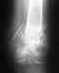

Снимки покажите, что там сейчас. Эндопртезирование в 28 лет - это не сильно радостный поворот.